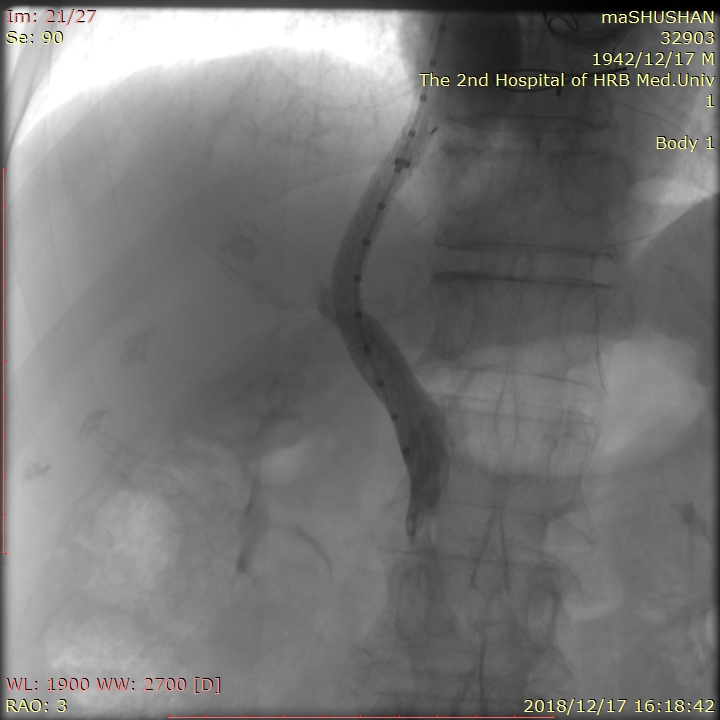

支架释放后再次进行门静脉造影,显示门静脉与下腔静脉通道建立

经过多次的研究讨论患者病情及充分的术前准备,白彬教授和王凯冰副主任医师为马大爷进行了TIPS手术。术中,白彬教授在患者的右侧颈部的静脉为穿刺入口,将导管置入肝门静脉内,经过测量患者门静脉压力达到31cmH2O,比正常人高出一倍;当白彬教授将支架植入肝静脉与门静脉之间建立起人工分流通道后,门静脉压力立即由31cmH2O降为15cmH2O,恢复到正常人的水平,达到彻底治疗目的。整个手术历时约2个小时,仅在马大爷右侧颈部、右侧腹股沟区留下两个3.5mm大小穿刺口。术后患者平安返回病房,继续进行抗感染、保肝、抗凝等治疗,目前,患者术后恢复良好。